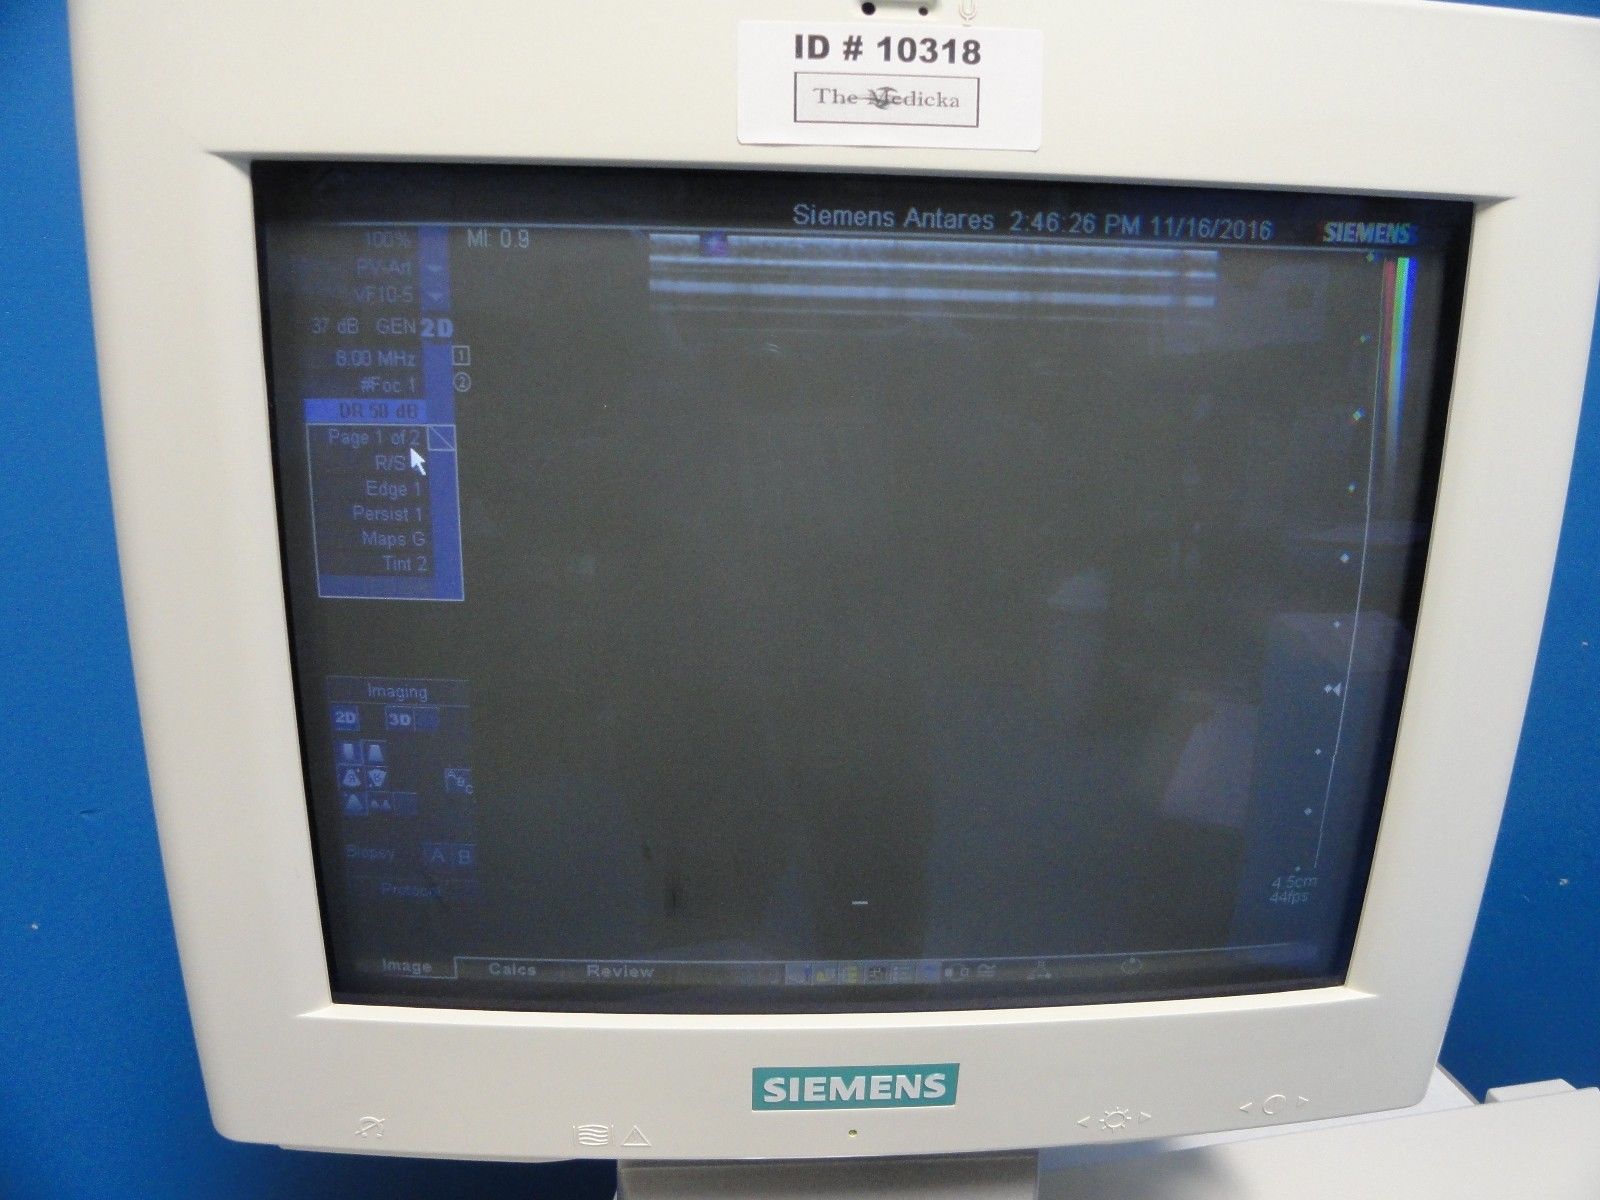

DIAGNOSTIC ULTRASOUND MACHINES FOR SALE

2017 GE ML6-15 -RS for GE S8 ,S6 Ultrasound

Sale price$ 7,675.18